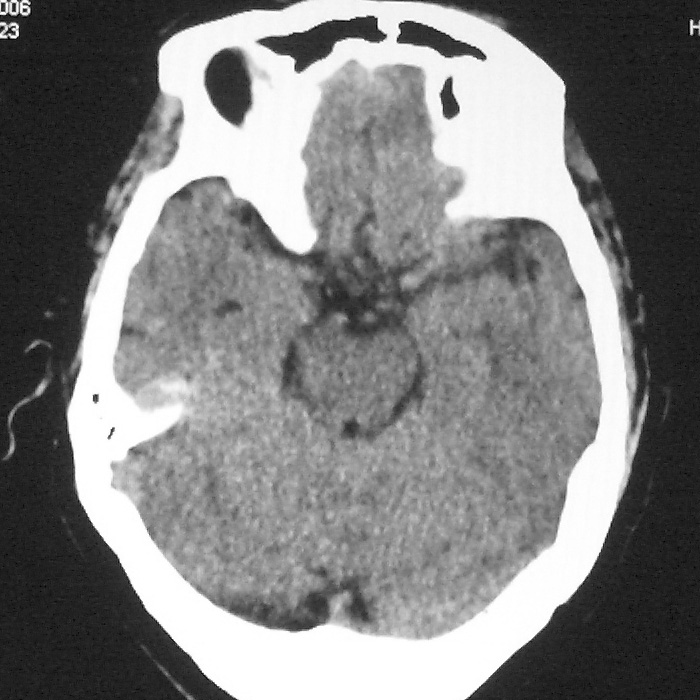

症状这么明显的话一般不会是单纯面神经麻痹引起的,最好做个mri,如果确实没有问题的话才能考虑面神经麻痹,毕竟这两种病的治疗和预后不一样,这个病人还有脑白质疏松。

左侧腔隙性梗塞灶,脑萎缩。

散在腔隙性脑梗塞.

皮层下动脉硬化性脑病。

双侧多发腔梗 脑萎缩